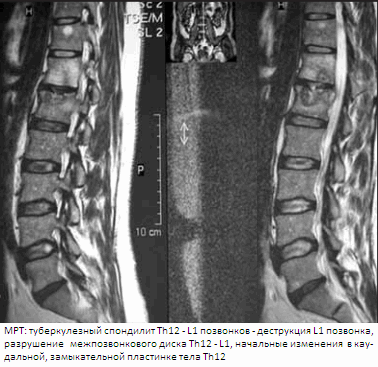

МРТ (магнитно-резонансная томография) обладает большим преимуществом при выявлении туберкулезного остита, позволяет прижизненно изучить динамику туберкулезного процесса, отражает протяженность паравертебральных абсцессов, дает возможность оценить состояние межпозвонкового диска, позвоночного канала, спинного мозга, его оболочек, компримирующего субстрата. Таким образом, показаниями к использованию МРТ являются: все случаи спинномозговых расстройств; необходимость уточнения протяженности компримированного участка спинного мозга; отсутствие изменений на рентгенограммах при наличии жалоб и клиники спинального дефицита; спондилит субокципитальной и шейно-грудной локализации; выявление абсцессов, их протяженности, связи с позвоночником и другими органами, в том числе при атипичном течении туберкулезного спондилита; сохраняющиеся неврологические нарушения после декомпрессивной операции. Использование МРТ не показано при наличии металлических конструкций в позвоночнике, искусственного водителя ритма сердца, металлических клемм на сосудах и др.

• Сагиттальные STIR и FSE T2 МР-И наиболее чувствительны в отношении диагностики отека костного мозга, поражения эпидурального пространства:

о МРТ считается наиболее информативной методикой, позволяющей оценить протяженность поражения и ответ на проводимую терапию